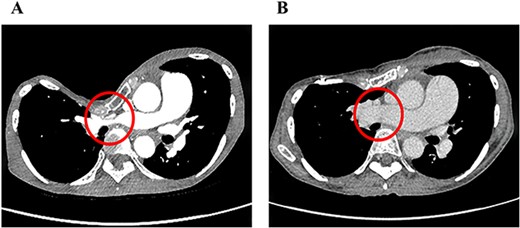

The clinical characteristics of the nine cases are summarized in Table 1. Median follow-up since our surgery is 53 months. The median age was 28 years (range, 16–74). These patients were categorized into two groups: eight patients with primary PE and one with PE recurrence after the Nuss procedure. Six had subjective symptoms such as palpitations and respiratory discomfort. Only one case had significant findings on preoperative echocardiography suggestive of pulmonary hypertension. In radiological findings, the HI–CT for PE was 15.4 (range, 6.3–29.3). One case had severe stenosis of the right main pulmonary artery due to sternal depression (Fig. 2A). The perioperative results of the CRN procedure are summarized in Table 2. Intraoperatively, no significant adverse events were noted. The median operation time was 223 min (range, 154–307 min) and the median volume of blood loss was 165 g (range, 10–904 g). The median length of hospital stay was 8 days (range, 6–37 days). Marked improvements in the HI–CT were seen in all cases (3.29, range, 2.72–4.96). In one case with stenosis of the right main pulmonary artery, not only did HI–CT improve, but also the diameter of the right main pulmonary artery increased from 5 to 20 mm after PE correction (Fig. 2B). Regarding postoperative complications, surgical site infections of the shallow layers were observed in two cases. No patient required re-operation due to adverse events.

Pre- (A) and postoperative (B) chest CT findings of severe PE with stenosis of the right main pulmonary artery. The diameter of the right main pulmonary artery increased from 5 to 20 mm after the CRN procedure.